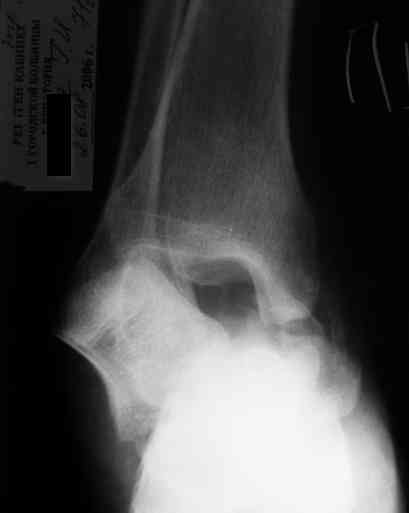

Уважаемый Александр! Как обещал представляю Р-граммы и операционные фото.

Опять надоедаю с вопросами:

Ваши (лично ваши) рекомендации - астрагалэктомия-аппаратный пяточно-большеберцовый артродез с одновременным удлинением голени - правильно?